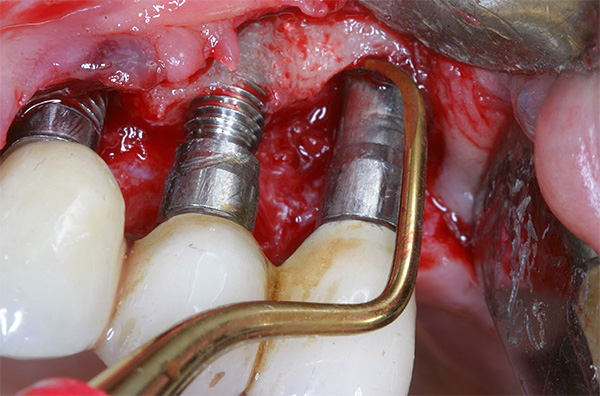

A foto abaixo mostra um exemplo de corrosão de um implante de baixa qualidade:

A qualidade do implante também desempenha um papel importante: quanto mais caro o sistema, mais materiais e tecnologias mais avançados são geralmente usados na fabricação da estrutura. As grandes empresas de implantes têm grandes orçamentos para gastar na melhoria de produtos e no desenvolvimento de tecnologias inovadoras.

A qualidade do enxerto e, portanto, o risco de possível rejeição, depende em grande parte do material de que é feito o implante (deve ser biocompatível com titânio com nosso corpo), bem como das características de sua superfície. Hoje, muitos fabricantes preferem um revestimento poroso - as células em crescimento do maxilar penetram nele, o que garante uma forte fusão de osso e implante.